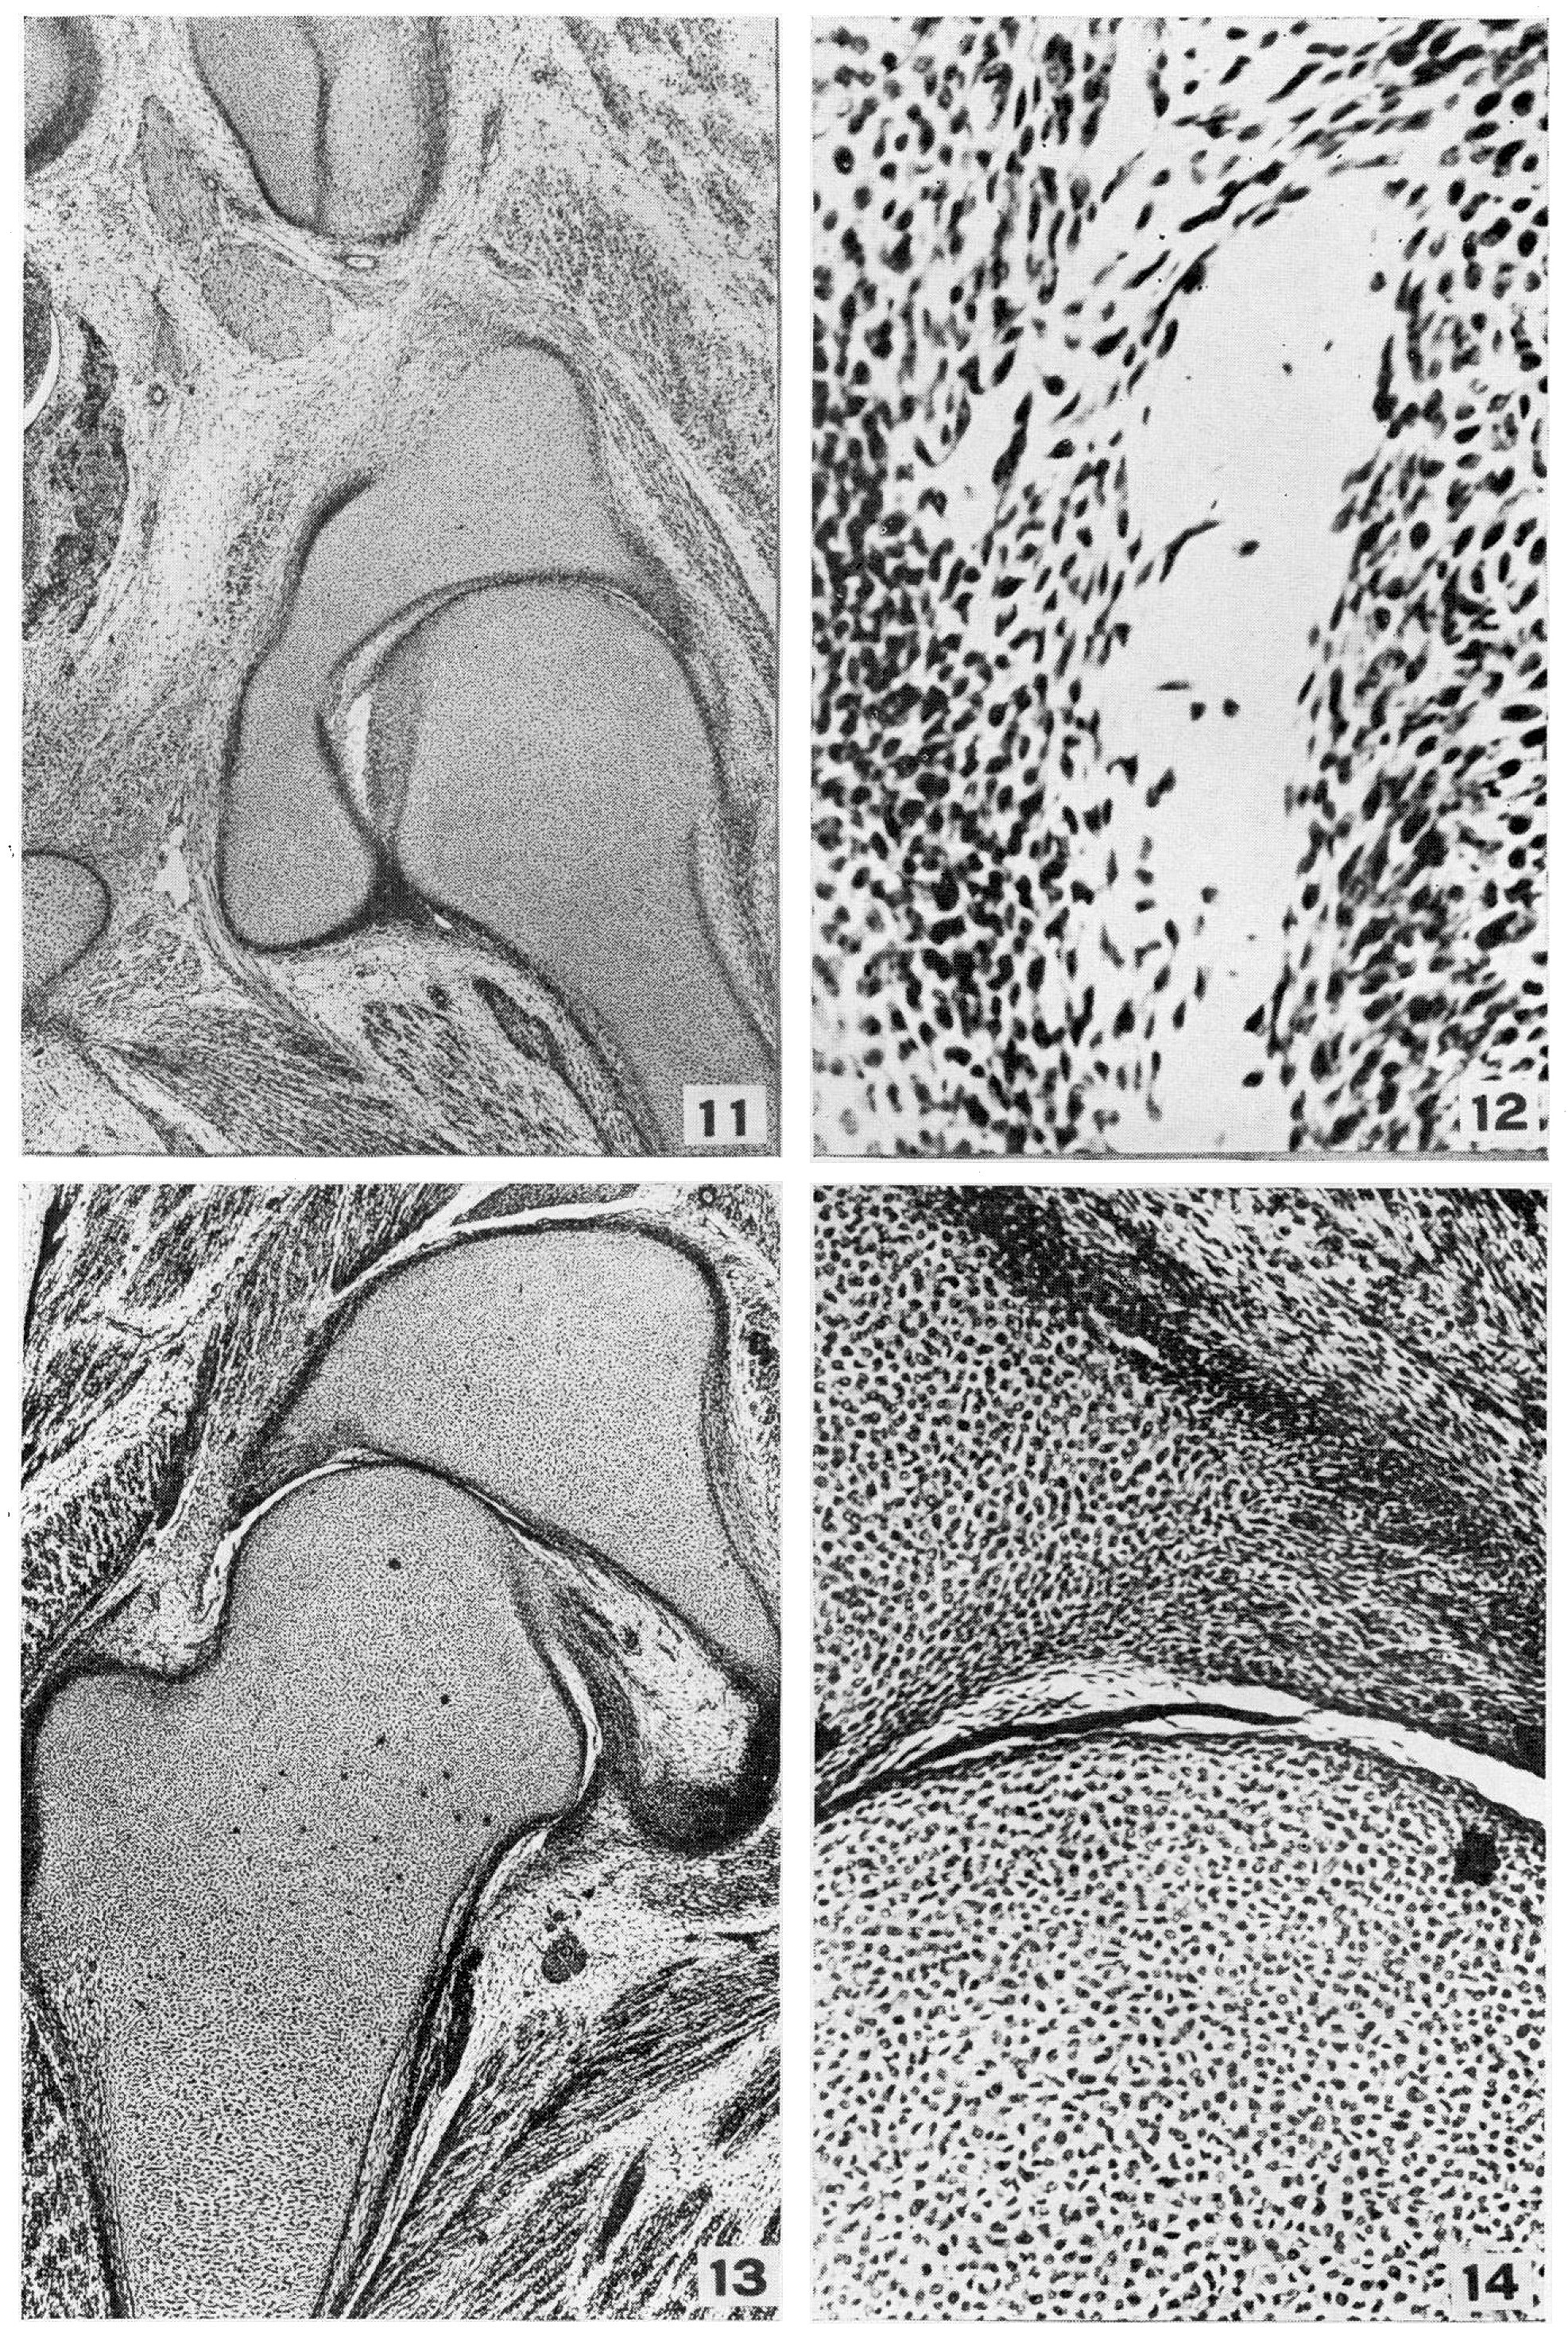

Evidence of a mechanical factor is found in observing the closely applied cartilaginous joint surfaces. In these areas the first signs of discontinuity are long strips of well-preserved cells stretched diagonally from the acetabulum to the head of the femur. Processes of the cells are so strongly attached to one another as apparently to stand considerable tension. The splitting does not occur at one level between the arched lines of cells. One end of a strand crossing the space may arise on the outer layer of the acetabulum and be inserted or attached to a layer 3 to 4 cells deep within the head of the femur. That this appearance might be an artefact can not be denied; however, of six embryos between 36 and 45 mm examined, the joint space of the 36 mm (Figs. 11 and 12) is well under way with no splitting of the cell layers. All the others, 37, 42, 44.3, and 45 mm respectively, show cell splitting along the joint margins as well as cell dissolution (Figs. 13 and 14). In Fig. 15 the space is well opened above and below the femoral neck. There are also strips of cells lying under the glenoid labrum. They are all larger than at 36 mm where the opening appears to be pure cell autolysis. If it were artefact, it could be expected to be marked most in the younger, least-developed embryos.

Fig. 11. Photomicrograph X20 H.E.C. Embryo 2059, length 36 mm, slide 2531. Spaces are- shown appearing in the tissue about the head of the femur. All the elements of the joint are defined. The acetabulum, glenoid labrum, and transverse acetabular ligament form 1800 of a circle. Blood vessels are present in perichondrium, joint capsule, ligamentum teres, and Haversian gland, but none, is present in the cartilage or shift of the bones.

Fig. 12. Photomicrograph X 140 H.E.C. Embryo 2050, length 36 mm, slide 2531. High power of space in Fig. 11. In the spaces float cells possessing normal-appearing nuclei and long fibrils. There are smaller cells with pyknotic nuclei as well as fragmented immaterial suggesting shadows of nuclei. The space s appear under time ligamentum teres, between it and the lead of the femur1li and within the capsule distal to the glenoid labrum.

Fig. 13. Photomicrograph X20 H.E.C. Embryo 838, length 42 mm, slide 1140. In two (Fig. 13 and 15) of 6 embryos examined at this stage a band from the ligamentum teres passes medially to the inferior margin of the acetabular fossa as well as to the transverse ligament, in addition to the usual ischial band. There is usually only a thin band of capsule arising from the pubis and ischium at this point.

Fig. 14. Photomicrograph X140 H.E.C. Embryo 838, length

42 mm, slide 1140. High power of Fig. 13. The lamellae of cells reaching

across the jointly show no signs of degeneration as is seen in Fig. 12. They

are spindle shaped and of the same character as those of the ligamentum teres. There

are no cuboid shaped synovial cells.